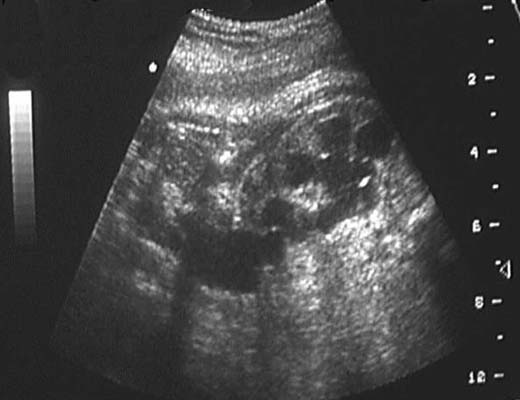

*Duplications :

- Disparité de calibre entre la dilatation calicielle supérieure et le pyélon inférieur, souvent moins dilaté.

- Mise en évidence de parenchyme rénal séparant les deux pyélons.

- Individualisation de deux uretères.

En cas de dilatation sur le seul pyélon supérieur, discuter une image kystique du pôle supérieur du rein :

La mise en évidence d’une dilatation urérétérale sous-jacente permet de faire le diagnostic.